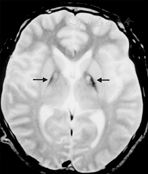

PKAN病例T2相上可见苍白球部位铁沉积显示低信号,而在苍白球的前内侧由于神经元死亡、胶质增生而显示高信号,这一影像学表现被称为"虎眼征"(图1)。"虎眼征"高度提示PKAN,但是极少数PANK2突变类型没有典型的"虎眼征",也有晚期患者随着铁沉积加重T2像上中间高信号消失而变成较均一的低信号。影像学上视神经、脑干和小脑一般不受累。